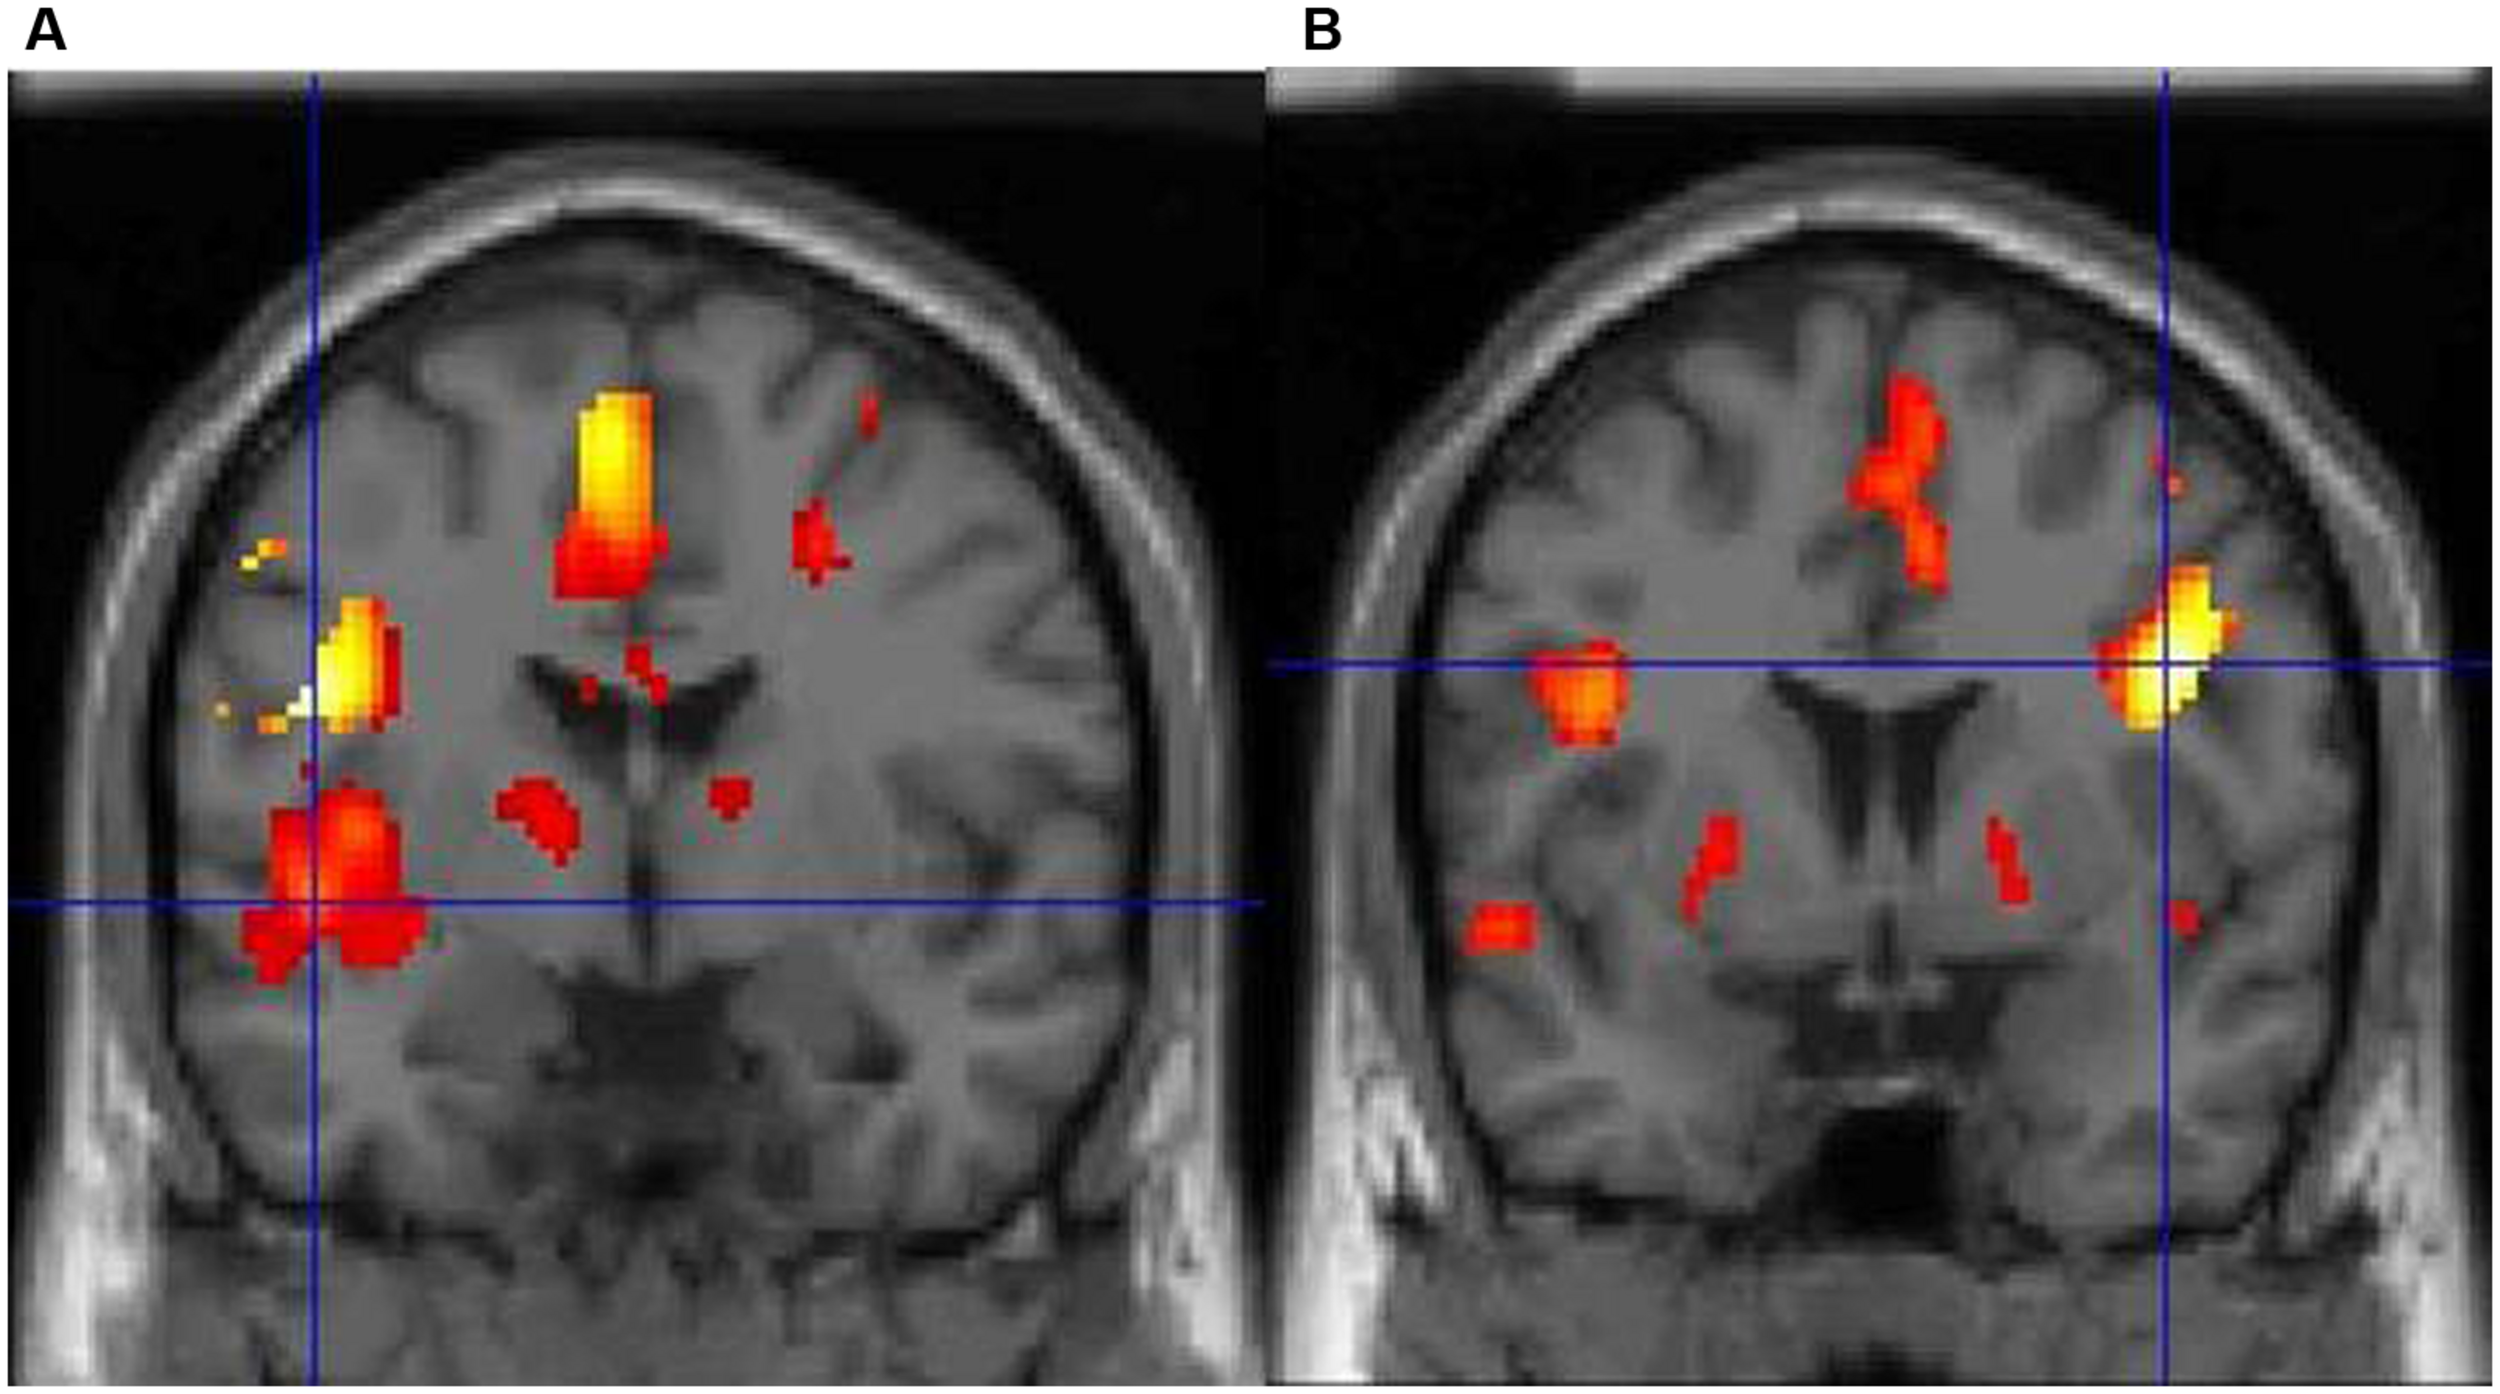

Dyslexia is primarily associated with a core speech sound (phonological) deficit (notably the inability to translate letters and letter patterns into phonological forms), with additional impairments in naming speed and working memory (Démonet et al., 2004; McCrory et al., 2005). In particular, dyslexics suffer from an inability to mentally represent words and speech sounds, or to break down complex entities into discrete sounds (Ziegler and Goswami, 2005). It should be noted that an alternative hypothesis postulates that phonological deficits emerge from visuospatial difficulties (Gabrieli, 2009; Vidyasagar and Pammer, 2010), but this is not the dominant theory currently (Skoyles and Skottun, 2009). Regardless of the cognitive bases of the disorder, dyslexia is rooted in a well-documented dysfunction of the reading network at the neural level. In particular, functional magnetic resonance imaging (fMRI) studies point toward functional and structural abnormalities in left parietal and temporal areas involved in phonological processing (Temple, 2002; Démonet et al., 2004), with compensatory engagement of anterior systems around the inferior frontal gyrus and a posterior (right occipital-temporal) system (Shaywitz et al., 2006; Waldie et al., 2013). For example, we have demonstrated that BOLD signal changes during lexical decision reveal striking differences in brain activity between typical readers and dyslexics (Waldie, 2002). The former consistently show a predominant activity in two areas of the left hemisphere, particularly in posterior (superior temporal) regions, whereas dyslexics display very limited left-brain activity, with significant activation only in the right inferior frontal cortex, probably as a compensatory system (Figure 1, Waldie, 2002).

FIGURE 1. (A) Typical adults show a predominance of activity in the left hemisphere during lexical decision-making with concrete nouns, particularly the left posterior superior temporal cortex (marked by the crosshair). (B) In contrast, adults with dyslexia show very limited left-brain activity and predominant activity in the right inferior frontal cortex.